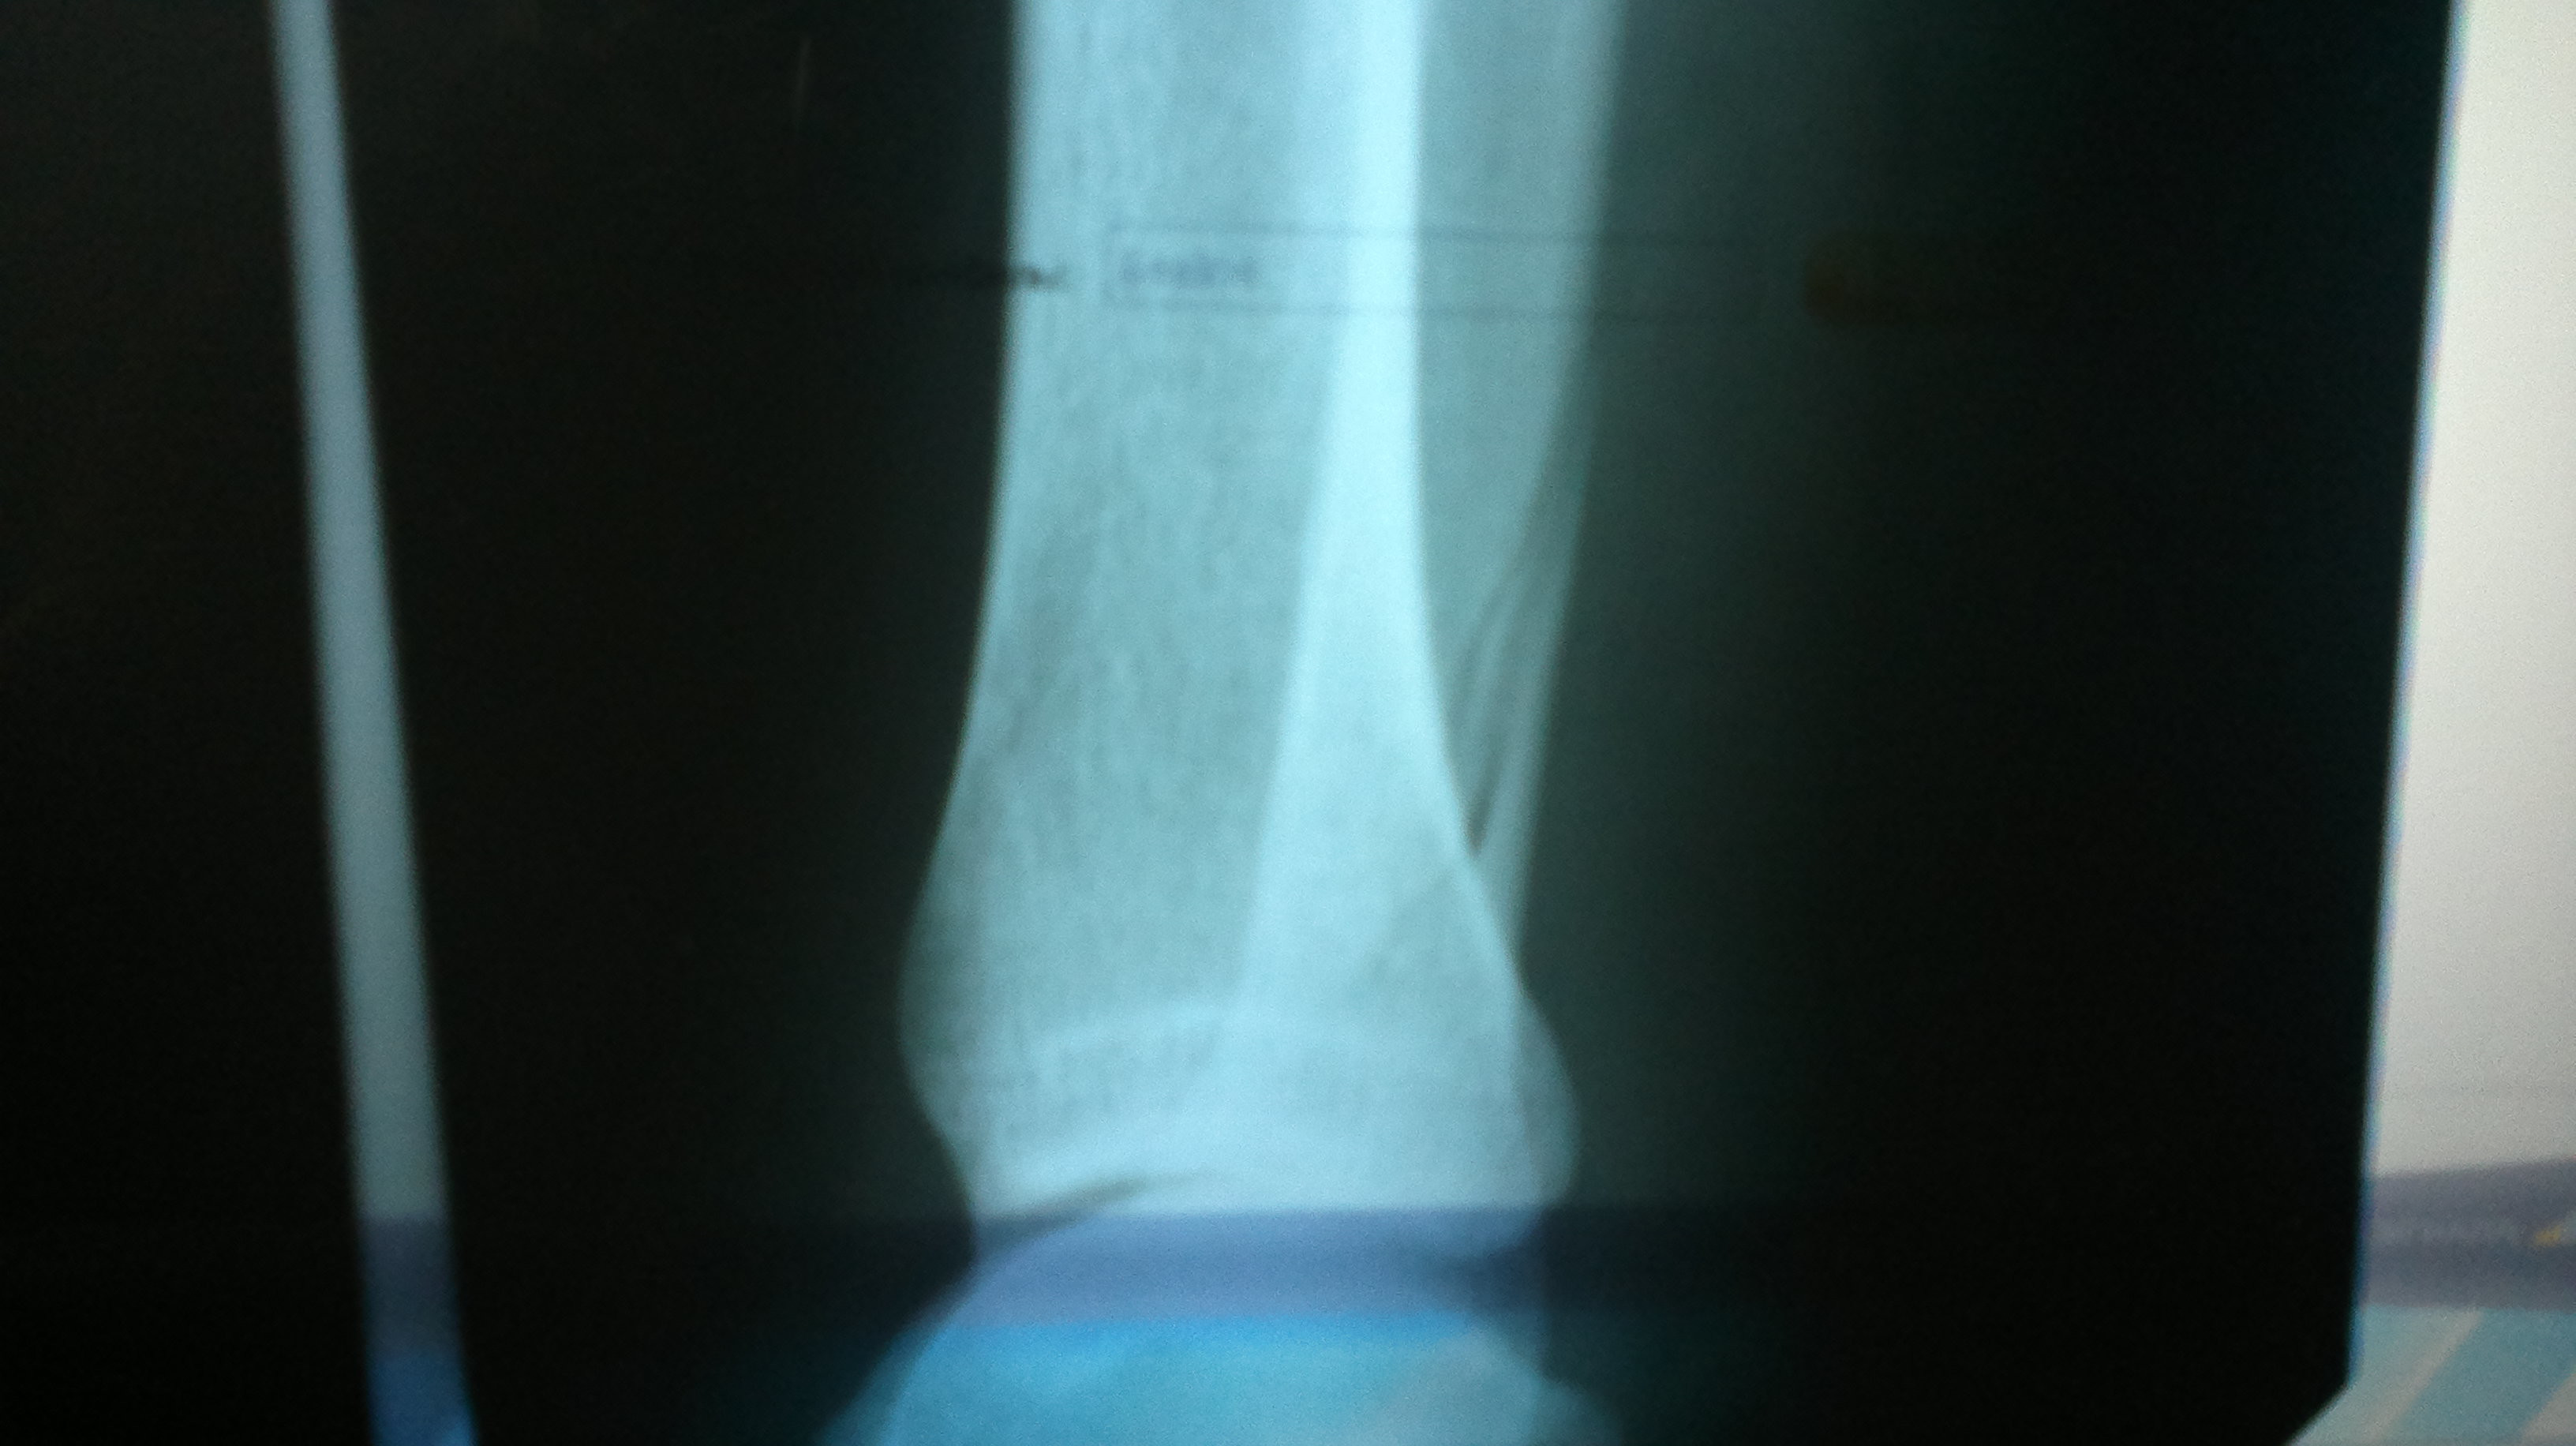

Понедельник. Время обхода. Зашел врач с зав. отделением спросил лишь такой-то такойтович, получив утвердительный ответ, оба быстро испарились настолько, что я не успел ничего ни сказать ни спросить. Только в обед вернулся лечащий врач и сообщил "У Вас закрытый винтовой перелом нижней трети большеберцовой кости со смещением". Из хороших новостей было лишь то, что мне не потребуется скелетное вытяжение, т.к. после травмы вовремя зафиксировали ногу и не произошло сильного смещения. Далее было предложено на выбор три варианта лечения - 1) Гипс до пояса минимум на три месяца и постельным режимом, 2) Остеосинтез пластиной, бесплатно, месяца два в постельном режиме и шрам 15-20см после операции. 3) Остеосинтез штифтом, и через неделю будете снова ходить на своих двоих (опять я наивный поверил, забыл врач добавить что на своих двоих с костылями), но у нас их нет, поэтому если хотите штифт, придется его купить, а поставим по ОМС (об этом будет отдельная история как я деньги за него возвращал).